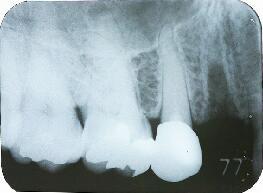

2ヵ月後のエックス線写真

1ヶ月半は咬合を控えた仮歯にて経過観察しその後最終かぶせ物の形を採りちょうど2ヵ月経過後メタルボンドポーセレンを装着してメンテナンスへ